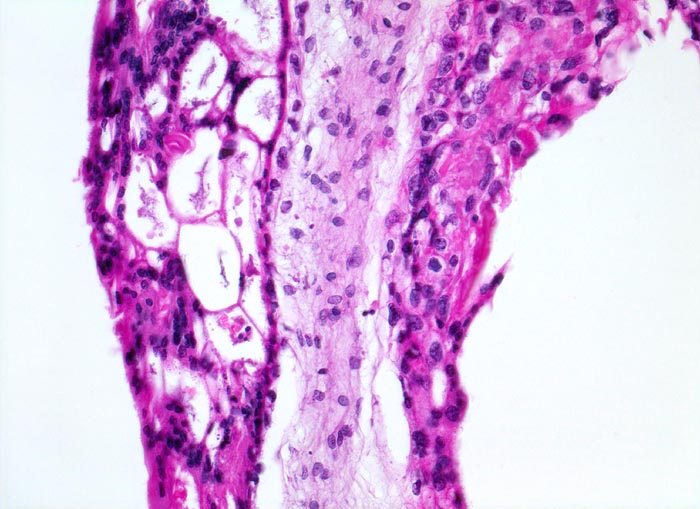

Makroskopisch ist die Plazenta deutlich grösser als erwartet für das Schwangerschaftsalter. Sie ist diffus von bis 2cm grossen Zottenblasen durchsetzt, welche nach Kollaps jedoch der makroskopischen Entdeckung entgehen können. Beim Aufschwemmen in Flüssigkeit entfalten sich die Blasen wieder. Mikroskopisch sind die Zotten aufgrund einer grobblasigen pseudozystischen Hohlraumbildung im Zottenstroma überwiegend grosskalibrig. Im Zottenstroma sind nur ganz vereinzelt Kapillaren nachweisbar. Im Gegensatz zu hydropisch geschwollenen Zotten im Sinne eines Regressionsphänomens zeigen die Zotten bei Blasenmole zusätzlich eine zirkumferentielle Hyperplasie von Synzytio- und Zytotrophoblast mit fakultativer Zellatypie. Bei herdförmiger Mole (> 3725) sind diese Veränderungen nur in einem Teil der Plazentarzotten ausgeprägt.

• Stark vergrösserte und verplumpte Plazentarzotten.

• Hydropisch umgewandeltes Zottenstroma ohne Gefässe mit Ausbildung von pseudozystischen Hohlräumen (Blasen)

• Trophoblastinklusionen und Kerntrümmer im Zottenstroma.

• Überschiessend proliferiertes Trophoblastepithel, teils in der gesamten Zirkumferenz der Zotten mit deutlichen Kernatypien. Kein Embryo.